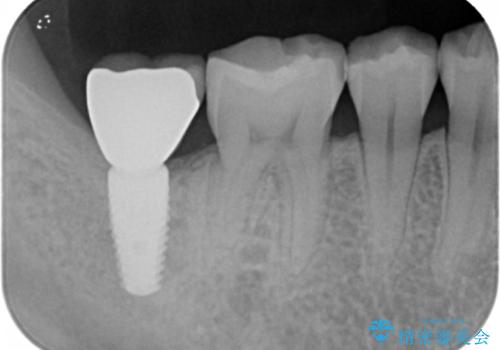

抜歯を行い、インプラントを入れていきました。

炎症で骨が少なかった場所には骨補填材を置いています。

高さがないため、スクリューリテインのインプラントの上部構造にしています。